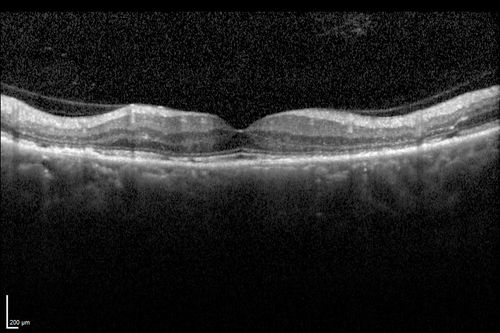

Chronic Central Serous Chorioretinopathy

77 year old man was seen at uveitis clinic and tested positive to  Anti-retinal antibody against 35 kDa and anti-optic nerve antibody.  He did not have EDI OCT, FAF, or ICG.  All testing was consistent with Chronic CSR.  His immunosuppresives were stopped and he did fine for 3 years.